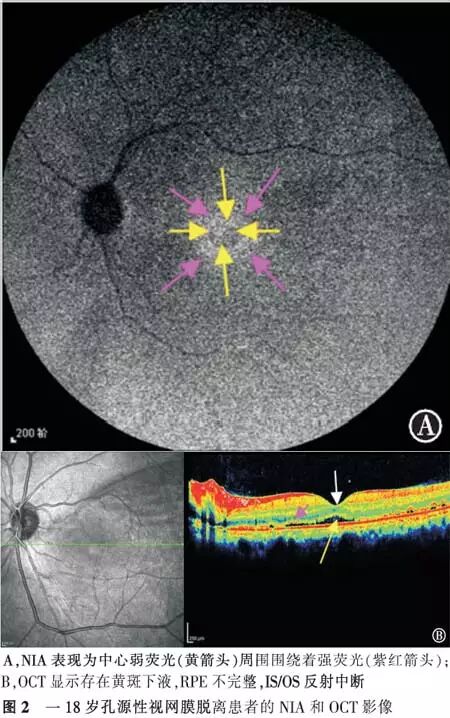

【摘要】 目的 近红外眼底自发荧光检查(NIA)联合OCT对孔源性视网膜脱离巩膜扣带术后早期黄斑结构的评估价值。方法 前瞻性系列病例研究。对21例(21眼)伴黄斑脱离的孔源性视网膜脱离患者行巩膜扣带术,于术后3个月行NIA及OCT检查。观察检查图像的异常和手术后视力的恢复情况。对视力的变化进行配对t检验,NIA与术后BCVA的相关性采用双向无序分类变量资料的关联性进行分析。结果 NIA:16眼表现为弱荧光周围围绕着强荧光,5眼表现为不均匀的强荧光。OCT:20眼存在黄斑下液;中心凹视网膜神经纤维层的厚度6眼变薄,14眼正常,1眼增厚;21眼IS/OS反射异常。视力恢复情况:术后3个月与术后1 d比较,NIA表现为弱荧光周围围绕着强荧光者,视力差异有统计学意义(t=9.922,P<0.05),NIA表现为不均匀强荧光者,视力差异无统计学意义(t=2.409,P>0.05),黄斑NIA表现与术后BCVA变化高度相关(C=0.502,P<0.05)。结论 孔源性视网膜脱离巩膜扣带术后早期,黄斑结构与功能均尚未完全恢复,需要我们加以重视。

【Abstract】 Objective To evaluate the changes in macular structure in the early stages after undergoing scleral buckling surgery for rhegmatogenous retinal detachment (RRD); to use melanin-related near-infrared fundus autofluorescence (NIA) combined with optical coherence tomography (OCT) for studing the changes. Methods This was a prospective case-series study. Melanin-related near-infrared fundus autofluorescence (NIA) and optical coherence tomography (OCT) examinations were performed on 21 patients with local primary RRD three months after undergoing a successful scleral buckling procedure for retinal reattachment. The RRDs in all 21 eyes involved the macula. To check the anomalies fo the images and the recovery of the vision after surgery. Changes invision after surgery were compared with a paired t test. The correlation of NIA and BCVA was analyzed with the relevance of two-way disorderly classification variable data. Results NIA revealed that 16 eyes had hypofluorescence surrounded by hyperfluorescence and 5 eyes had uneven hyperfluorescence. Submacular fluid was found in 20 eyes. The retinal nerve fiber layer in the central fovea became thinner in 6 eyes. In one eye, the retinal nerve fiber layer in the central fovea became thicker, and in another 14 eyes the thickness of the retinal nerve fiber layer was normal. The reflection from the photoreceptor inner and outer segment junction (IS/OS) was abnormal in all 21 eyes. Visual acuity measured with NIA revealed that the hypofluorescence which was surrounded by hyperfluorescence had improved at the 3-month follow-up compared to the 1-day follow-up examination (t=9.922, P<0.05), while VA measured at the same time revealed that uneven hyperfluorescence had not improved at the 3-month follow-up (t=2.409, P>0.05). The macular NIA results and the change in postoperative BCVA were highly correlated (r=0.502, P<0.05). Conclusion Macular function and structure do not fully recover in the early stages after undergoing scleral buckling to treat RRD. More attention should be paid to this problem.